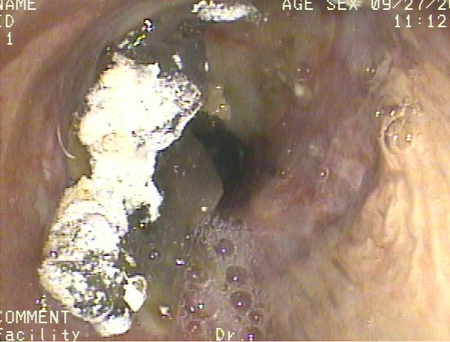

Aspiração aguda

Broncoscopia mostrando aspiração de bário para o brônquio principal direito depois de um estudo de esofagografia baritada em um paciente com pulmão transplantado

Do acervo de Dr. Kamran Mahmood